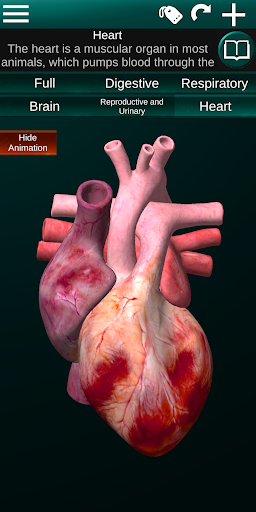

Toont een 3D-anatomisch model van de belangrijkste organen van het menselijk lichaam en een beschrijving van elk orgaan.

* Hart, dat de atria, ventrikels, aorta en een animatie van dit orgel omvat.